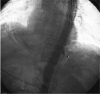

Interventions: An endovascular stent graft was placed under the guidance of digital subtraction angiography and followed by antibiotic therapy to prevent infection and proton pump inhibitor therapy to inhibit gastric acid secretion.